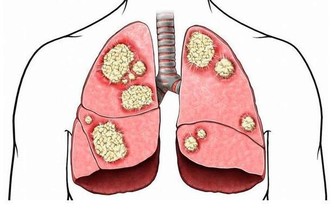

中醫提及,有心血管疾病的患者,多半有不明原因的頸部酸痛、喉嚨痛、胸痛、胃痛,甚至小指內側、靠近無名指的整條手少陰心經會麻、有緊縮感,所以問診時就會特別留意。

食指下的第二掌骨直接對應全身,從最靠近指尖的位置算起,分別對到:頭、頸、上肢、肺心、肝、胃、十二指腸、腎、腰、下腹、腿足,堪稱是人體縮小版。